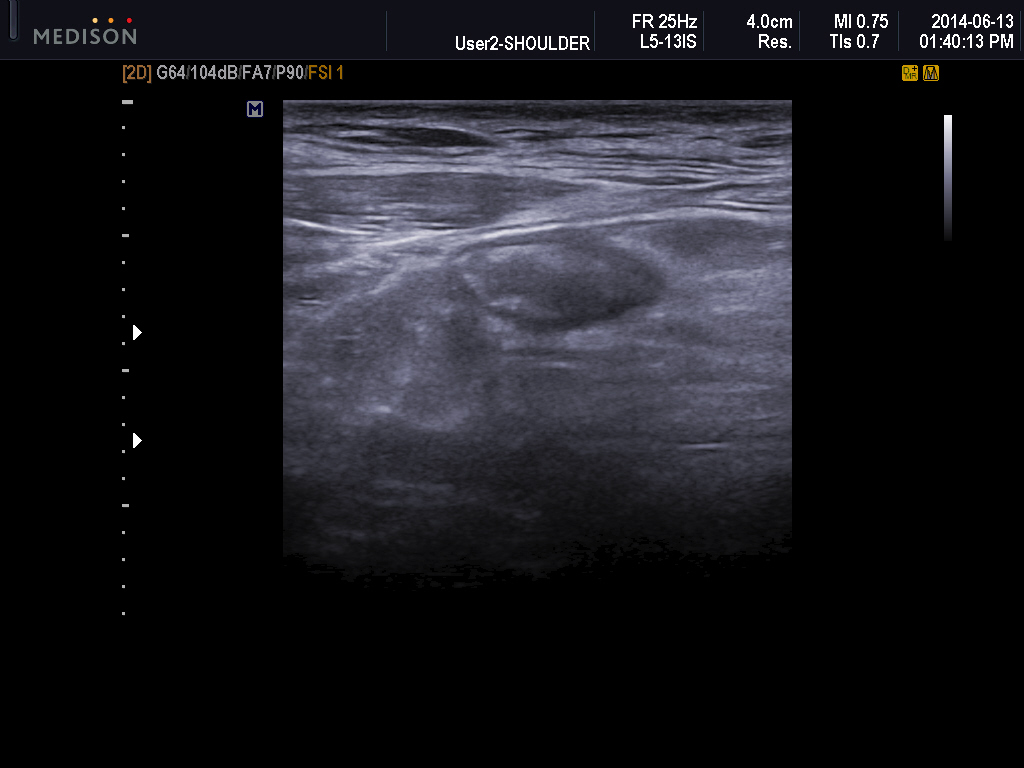

Ultrasonographic data of our patients